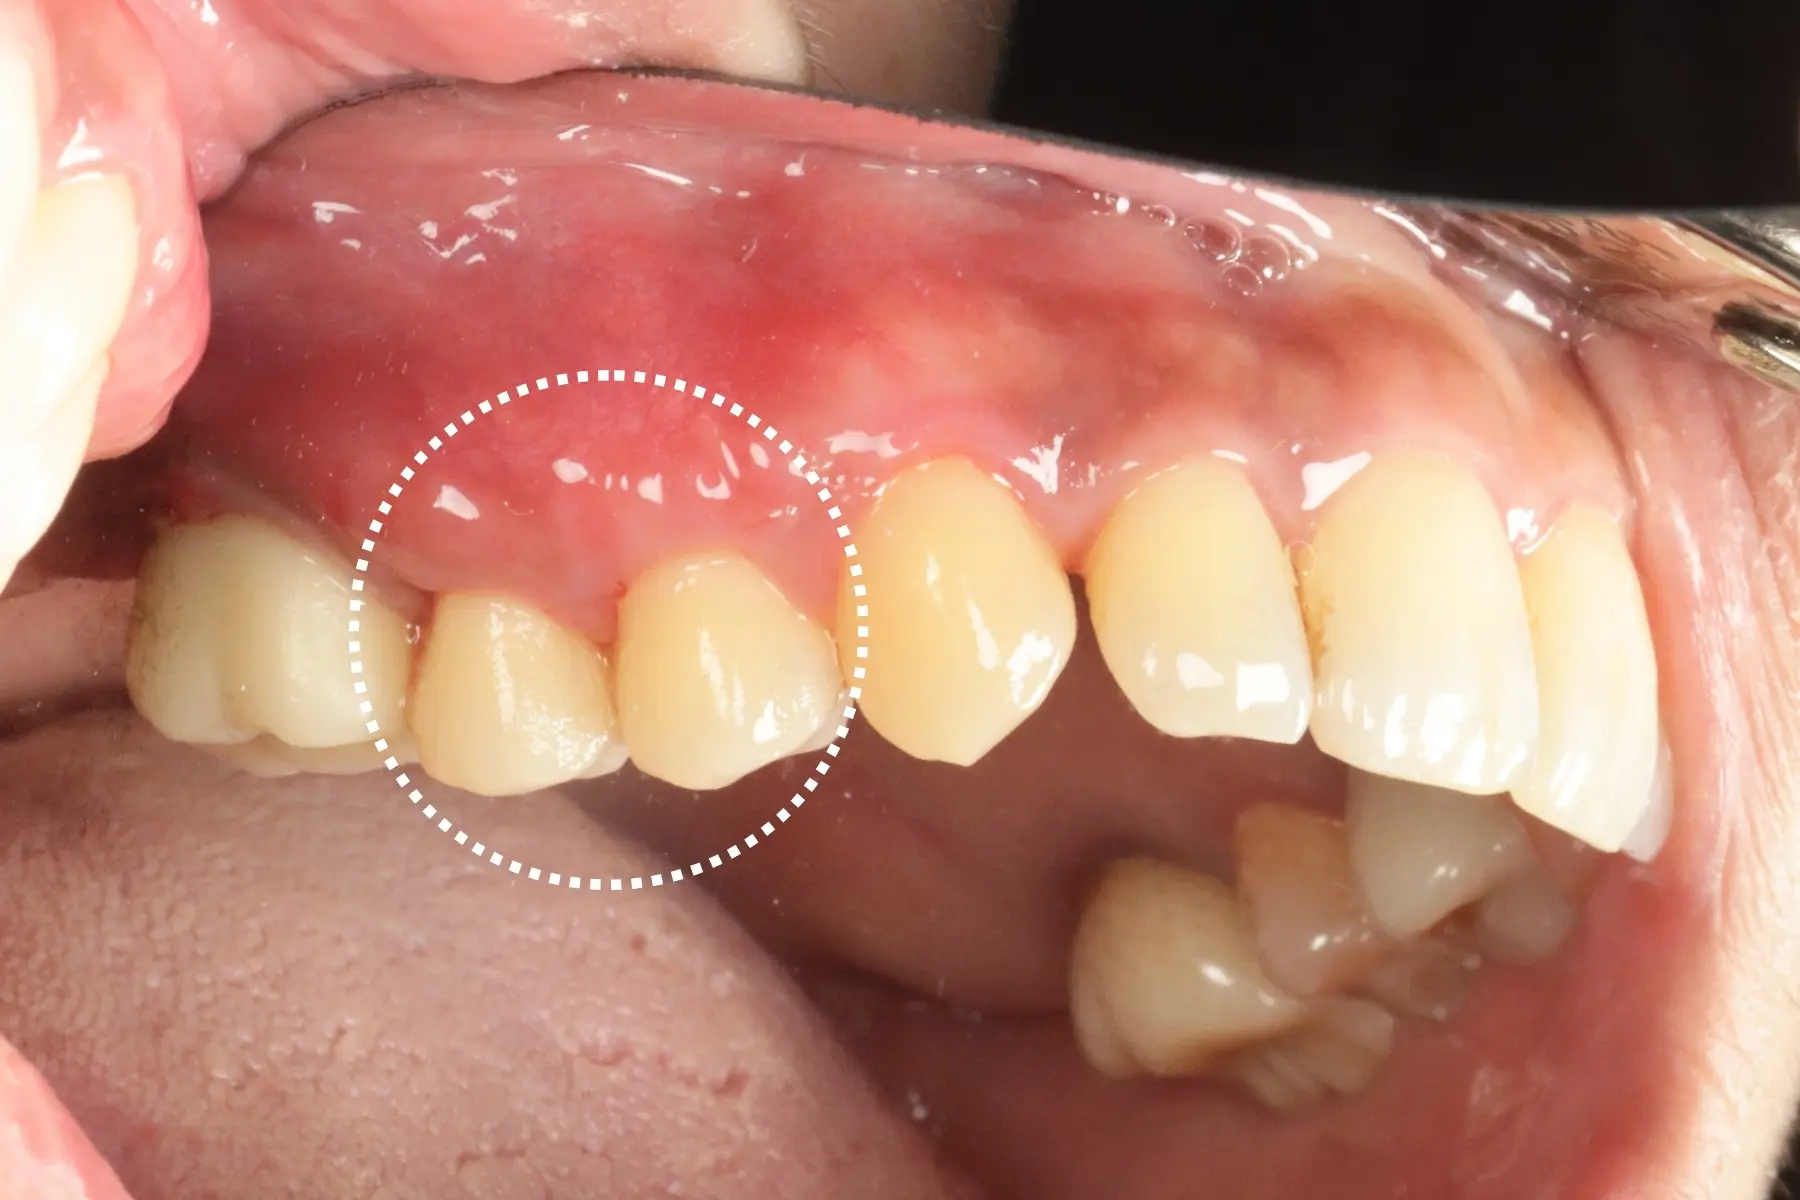

• 術前 42

術後 40

牙周治療

主治醫師

• 鍾國耀

治療時間

三次療程

主訴

右上前牙牙齦反覆腫脹化膿